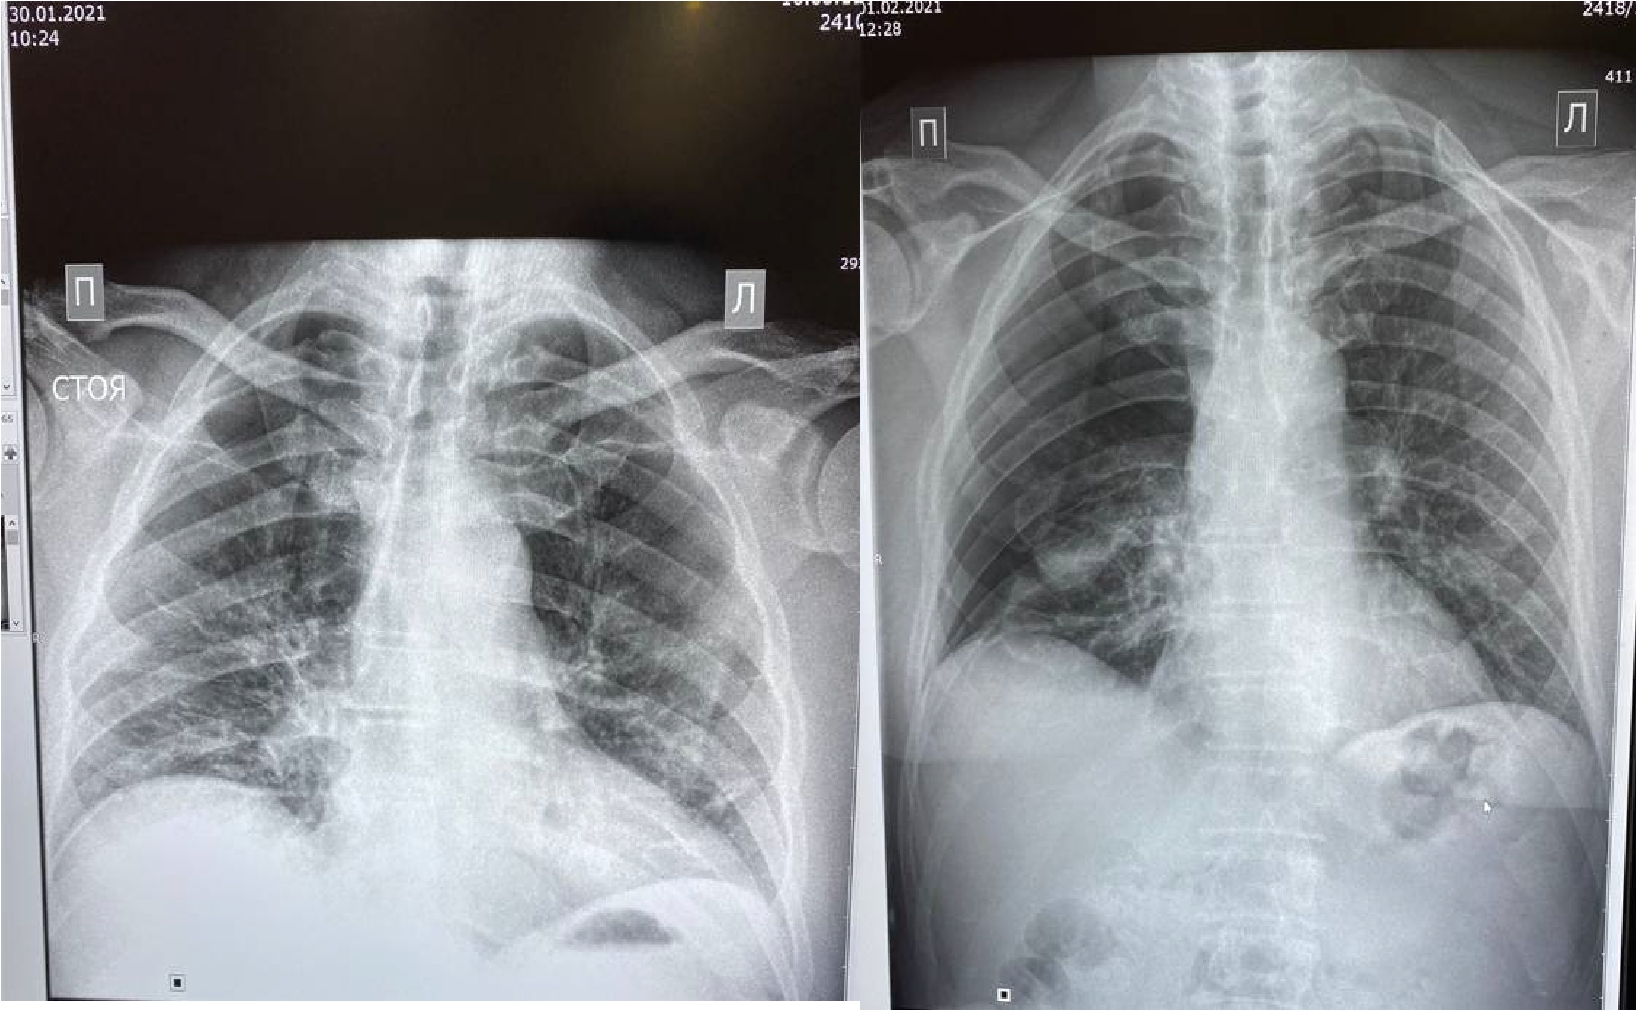

Проведено дренирование плевральной полости справа по Бюлау. В результате отмечена отчетливая положительная динамика в виде устранения одышки, повышения SpO2. Через 3-е суток при контрольной рентгенографии органов грудной клетки выявлен верхушечный пневмоторакс справа (рис. 6), проведена пункция плевральной полости, дренирование продолжено. На фоне устойчивой положительной динамики в дальнейшем, на 23-е сутки терапии пациент выписан в удовлетворительном состоянии.

Рисунок 6. Рентгенограмма органов грудной клетки – признаки двусторонней полисегментарной интерстициальной пневмонии (объем поражения 30%, КТ-2). Верхушечный правосторонний пневмоторакс